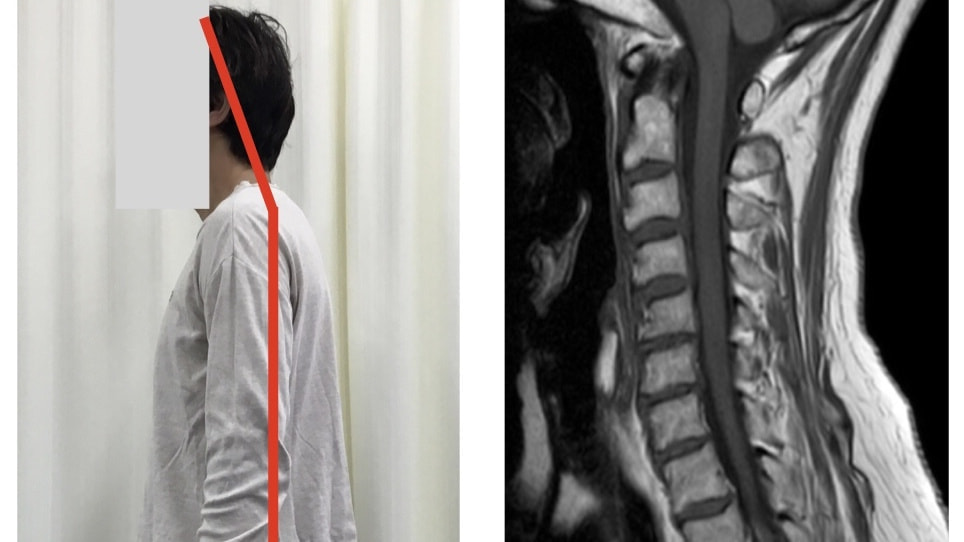

頚椎は、頭部を支えたり衝撃吸収を行う為に、前方へ弯曲しています。

これが「何かしらの影響」により骨の位置異常が起こると、「ストレートネック」や「頚椎ヘルニア」といった障害に繋がっていきます。

この「何かしらの影響」は、日常生活動作(長時間のデスクワークやスマホ使用など)や癖も関係しており、頚椎にある場合もあれば背部や肩など別部位からの問題で発生することもあるため、何処に原因があるかを明確に判断していく必要があります。

実際の症例報告はこちら。

➝「頚椎ヘルニアについて